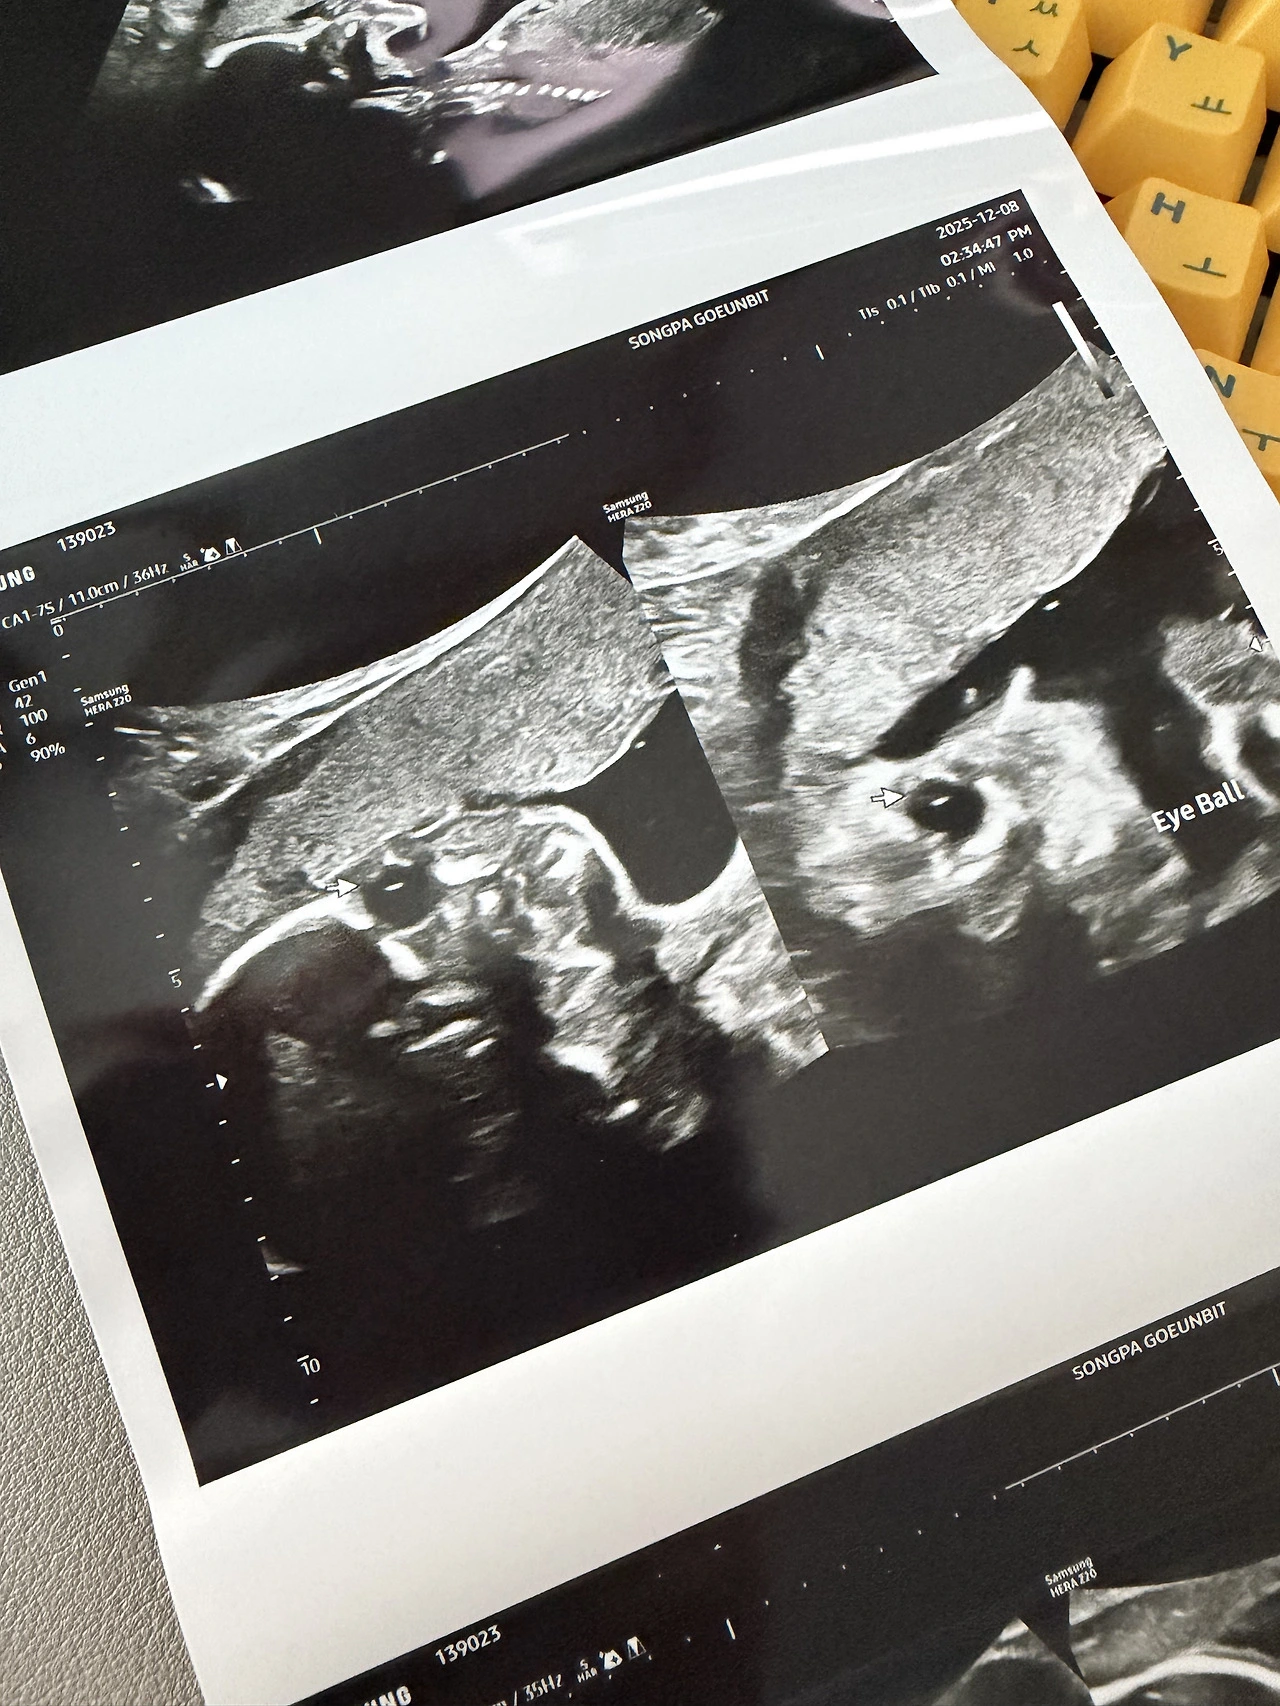

드디어 정밀초음파를 보는 날이 되었다. 난임병원과 분만병원의 커뮤니케이션 이슈 때문에 1차 기형아 검사때 대부분 한다는 정밀초음파를 보지 못해서 조금 불안했었는데 이번에야 말로 볼 수 있어서 정말 다행이었다. 정밀 초음파는 아기가 협조하는 가정하에 20분 남짓 보는데 주로 심장의 발달에 대해서 주의깊게 본다. 좌심방 우심실.. 판막.. 이런 생물시간에 들었던것 같은 용어들을 오랜만에 들어 볼 수 있었다.

눈과 귀가 제대로 있는지 입도 잘 생겼는지 손가락 발가락도 5개씩 잘 발달했는지를 낳기도 전에 초음파로 미리 확인 할 수 있다고 하니 임신 기간 내내 더 없이 좋았다. 더욱이 첫 정밀 초음파이다보니 기대보다는 걱정이 좀 더 많았던 것이 사실이다. 아기가 잘 협조해 준 덕분에 20분 남짓 빠르게 정밀 초음파를 볼 수 있었고 사실 이 중에 10분은 심장을 세밀하게 봐서 엄마가 봐도 잘 모르는 부분이 대부분이다.

"초음파로 확인 할 수 있는 부분 모두 정상입니다. "